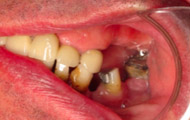

Situation clinique initiale